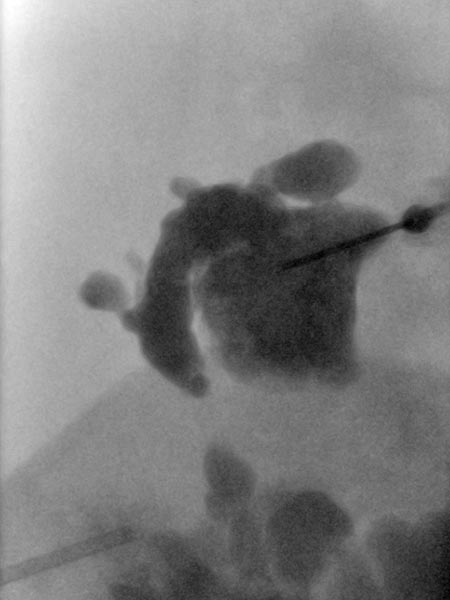

Übersichtröntgenbild im Bereich der rechten Beckenschaufel nach Injektion von Kontrastmittel über die in der LM liegende Nadel. Es kontrastieren sich aus dieser Nadellage weite Anteile der LM, damit optimale Position für die Sklerosierung.

Makrozystische lymphatische Malformationen (LM), die direkt an der Haut liegen, können durch den hohen lokalen Lymphdruck zu einem Durchtritt von Lymphflüssigkeit durch die Haut über kleine Hautbläschen (Lymphvesikel) führen. Diese Areale werden Lymphangioma circumscriptum genannt. Durch eine Sklerosierungstherapie (hier mit Picibanil = OK-432) werden die Lymphkanäle über eine starke lokale Entzündung verschlossen und die Haut abgedichtet. Günstig in diesem Fall die größeren Anteile der lymphatischen Malformation, die miteinander kommunizieren (nach Injektion von KM über die Punktionsnadel sichtbar). Daher sind nur wenige Punktionen notwendig um die gesamte lymphatische Malformation zu sklerosieren. Dieses minimalinvasive Verfahren ist meist auf Dauer schonender als offen operative Maßnahmen, da einzelne, auch kleine Kammern in den oft fuchsbauartig verzweigten LM mit dem flüssigen Sklerosierungsmittel leicht erreicht werden können.